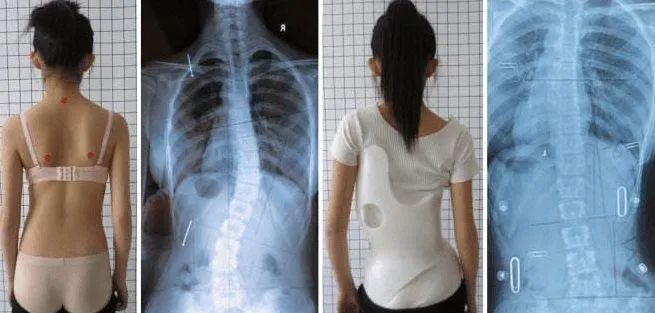

脊柱側(cè)彎是一種表現(xiàn)為脊柱旋轉(zhuǎn)不對稱的疾病。兒童青少年脊柱側(cè)彎主要指兒童青少年特發(fā)性脊柱側(cè)彎,長期姿態(tài)不良是青少年脊柱側(cè)彎的最常見原因之一。

有脊柱側(cè)彎的人,嚴(yán)重影響美觀,除了對孩子造成生理上的影響,還會產(chǎn)生自卑等心理問題;脊柱側(cè)彎發(fā)展到一定程度會影響內(nèi)臟器官發(fā)育,引起慢性疾病,還可使近視發(fā)生風(fēng)險(xiǎn)升高47.2%。

繼肥胖、近視后,脊柱側(cè)彎已成為危害我國兒童及青少年健康的第三大“殺手”。如不及時(shí)發(fā)現(xiàn)、治療,其影響會一直持續(xù)到成年、老年。青少年時(shí)期是脊柱側(cè)彎矯正的黃金時(shí)期,早期脊柱側(cè)彎篩查與康復(fù)介入,能夠促進(jìn)體態(tài)恢復(fù),降低手術(shù)概率。

如果自測發(fā)現(xiàn)存在脊柱側(cè)彎的可能,請盡早前往醫(yī)院進(jìn)行診斷。滕州市中心人民醫(yī)院理療科門診設(shè)有脊柱側(cè)彎中醫(yī)藥干預(yù)門診,免費(fèi)為您提供篩查服務(wù),并根據(jù)每一位患者的側(cè)彎類型、程度和特點(diǎn),給予個(gè)性化專業(yè)矯正方案。通過理療、艾灸等中醫(yī)特色,結(jié)合運(yùn)動康復(fù),幫助兒童青少年改善體態(tài),矯正脊柱側(cè)彎。